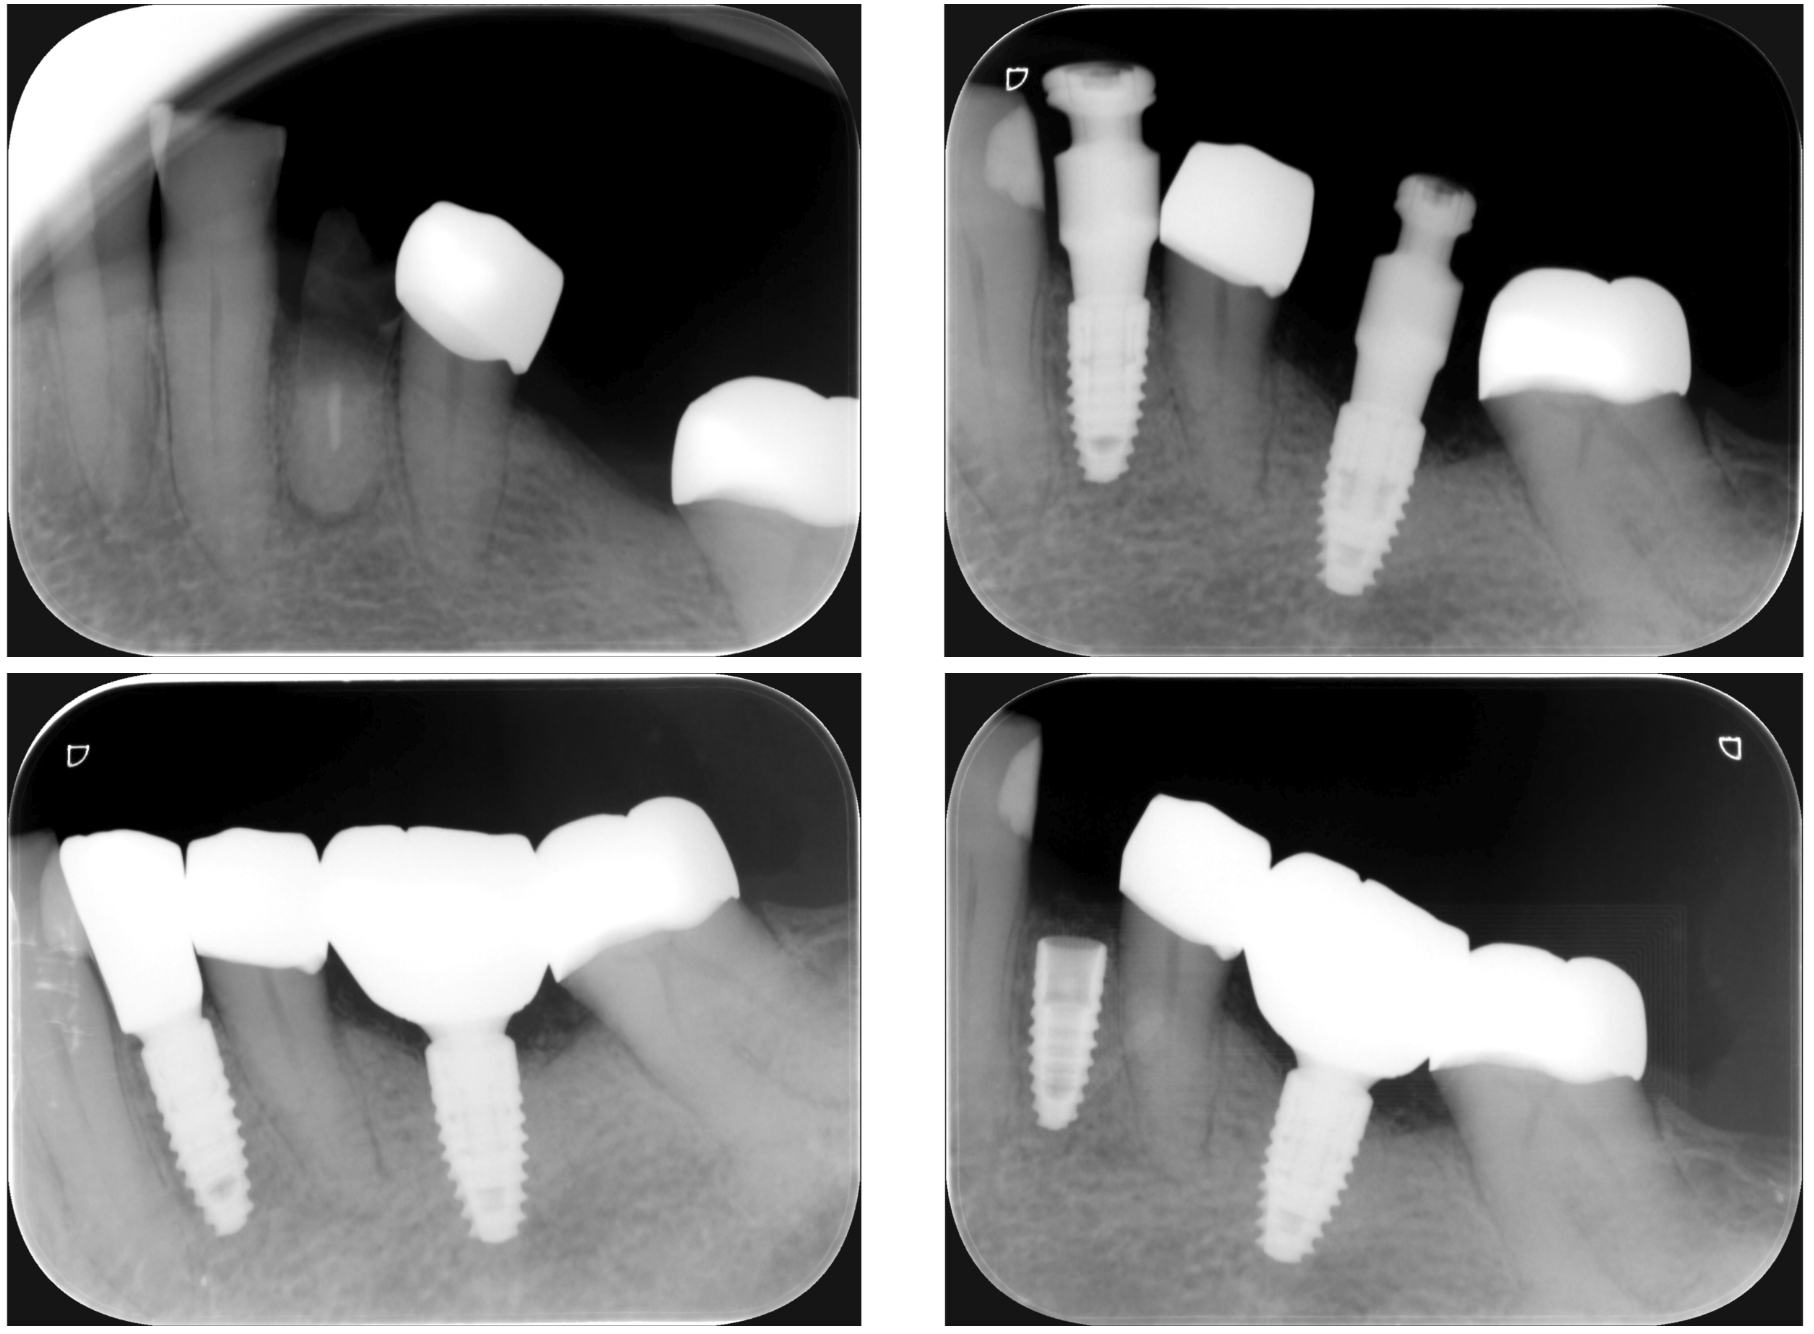

Dental implants are one of the most advanced solutions for replacing missing teeth—designed to restore not just your smile, but also your ability to chew, speak, and live confidently. A dental implant acts as a new tooth root, made from titanium and placed into the jawbone. It supports a crown or bridge, creating a replacement tooth that looks, feels, and functions like a natural one.

A dental implant consists of three main parts:

- Implant fixture – a titanium root placed into the bone

- Abutment – a connector between implant and crown

- Crown – the visible tooth, custom-designed for aesthetics and function

The result is a stable, long-term tooth replacement that integrates with your body through a biological process called osseointegration.

Dental Implants vs. All-on-4

Dental implants can be used for a single tooth—or a full arch.

- Single Implant: replaces one missing tooth

- All-on-4: uses 4–6 implants to support an entire arch

- Single implant = one pillar per tooth

- All-on-4 = strategic pillars supporting a full structure

3. Implant Placement

Titanium implant is placed into bone → healing phase (2–3 months).

4. Final Restoration

Abutment + custom crown (ceramic / zirconia) placed for final result.